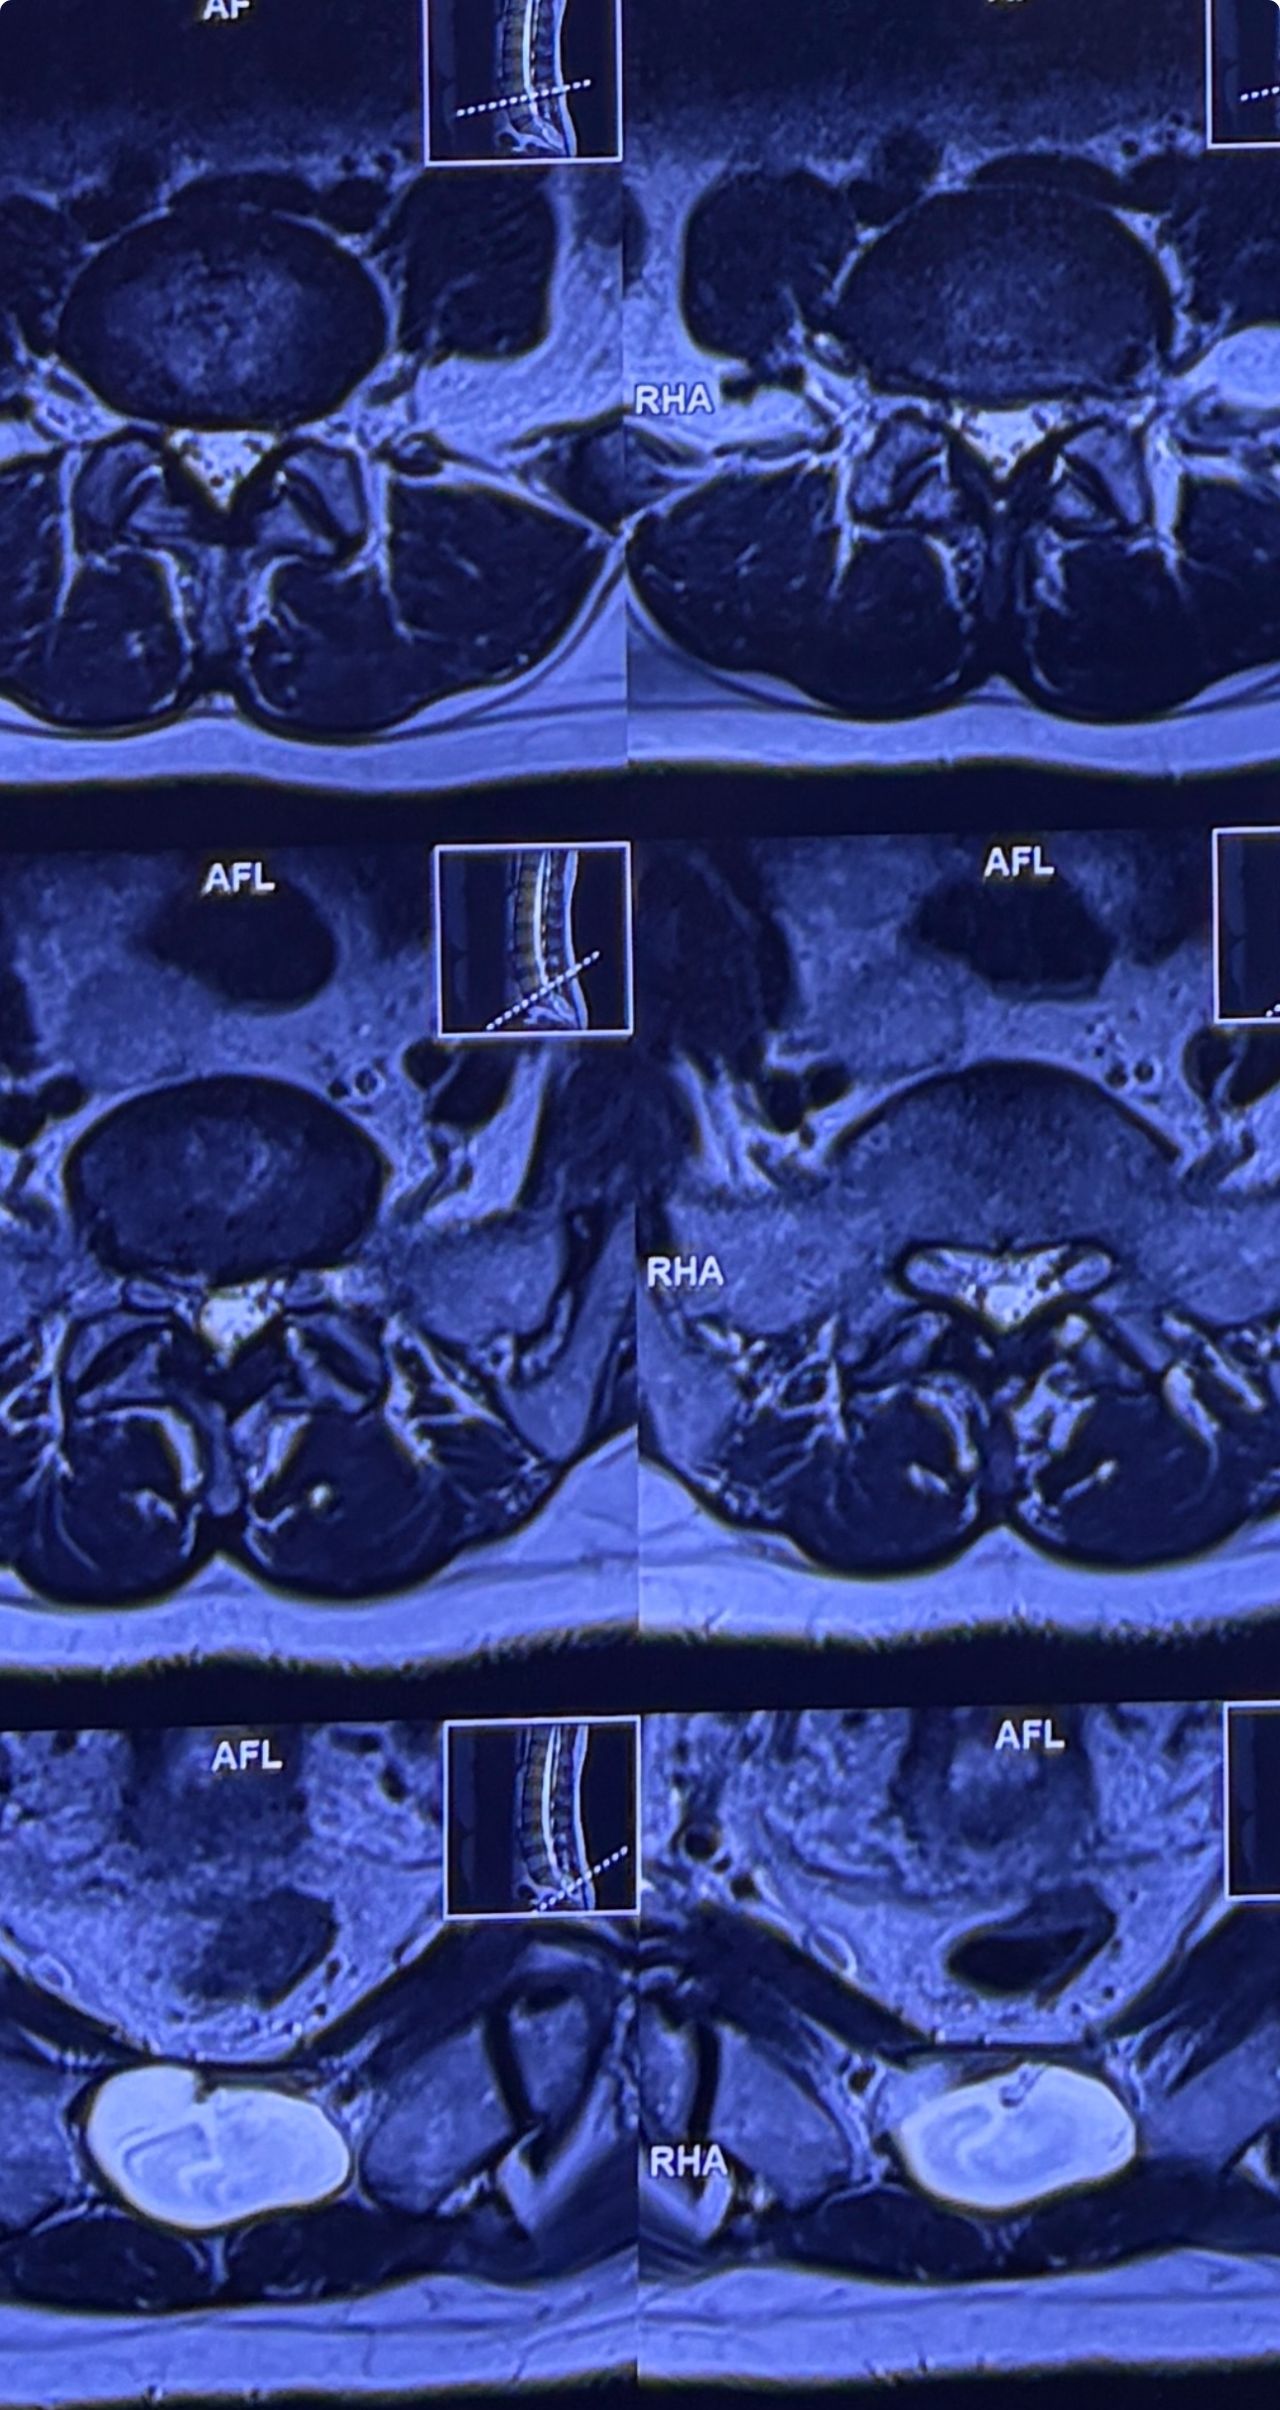

46 years old female patient presented to my clinic yesterday june 1/2025 with LBP and radicular L leg pain for several months which hasn’t responded to physio 2 neurosurgeons have visited her and didn’t suggest any surgery Neurological exam was unremarkable please see her mri/ emg/ncv and her huge tarlov cyst and possible L IVF L4-5 hyperbulge I ordered sacrum mri and ct scan and new emg/ncv and asked her with her sacral Ct scan and MRI first sees another two famous neurosurgeons and see if that large cyst is the reason for her pain if not i can work on her L4-S1 area Do you think her radicular pain can originate from her large cyst in sacrum? Do you consider surgery and removing her sacral cyst?